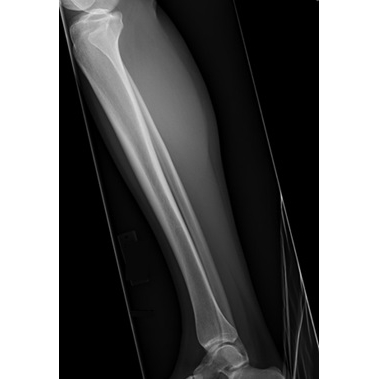

The patient reported acute onset of right lateral knee pain after being slide-tackled during a soccer match five days earlier. She experienced a varus force to her knee as she went for the ball. She reported a sensation of "popping out" at the lateral aspect of her knee at the time of injury. She stated that she had a visible deformity noted to the lateral inferior aspect of her right knee, which was self-resolved by the time she presented to a local ED for initial evaluation. She did not recall exactly how or when it reduced. She was unable to bear weight immediately after the injury. In the ED, radiographs were obtained Case Photo #1 Case Photo #2 Case Photo #3 Case Photo #4 which were negative for acute fracture or dislocation. The patient did not recall the diagnosis, but was recommended a compression wrap, crutches, and analgesics. She was advised to follow up with Sports Medicine. She presented to the Sports Medicine clinic with continued right lateral knee pain with weight-bearing, knee instability, and right anterolateral ankle pain. She reported minimal knee or ankle swelling. She denied symptoms of catching, clicking, locking, skin changes, or lower extremity paresthesias. She had no prior history of injury to the right knee.